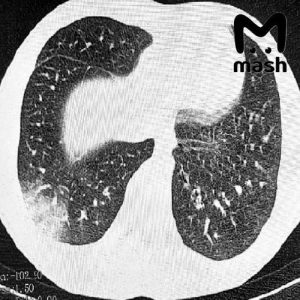

Троих зумеров экстренно доставили в реанимацию Ростовской области с попкорновой болезнью лёгких — которая развилась из-за постоянного курения вейпов

Ещё одно доказательство, что вейпы абсолютное зло… У 16-летнего пациента — серьёзная дыхательная недостаточность, потребовалась искусственная вентиляция лёгких. У другого — двусторонняя вейп-ассоциированная пневмония EVALI, врачи сделали операцию. Похожие случаи фиксируют и в других регионах России: первые в Москве в 2021-м, затем в Томске, где в прошлом году пострадали двое несовершеннолетних. Врачи говорят: электронки серьёзно …